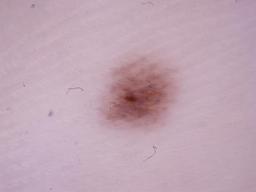

{

"age_approx": 20,

"anatom_site_general": "lower extremity",

"concomitant_biopsy": true,

"diagnosis_1": "Benign",

"diagnosis_2": "Benign melanocytic proliferations",

"diagnosis_3": "Nevus",

"diagnosis_confirm_type": "histopathology",

"image_type": "dermoscopic",

"lesion_id": "IL_0636666",

"melanocytic": true,

"sex": "female"

}